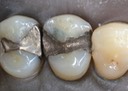

Joe Cha #3 pre-op